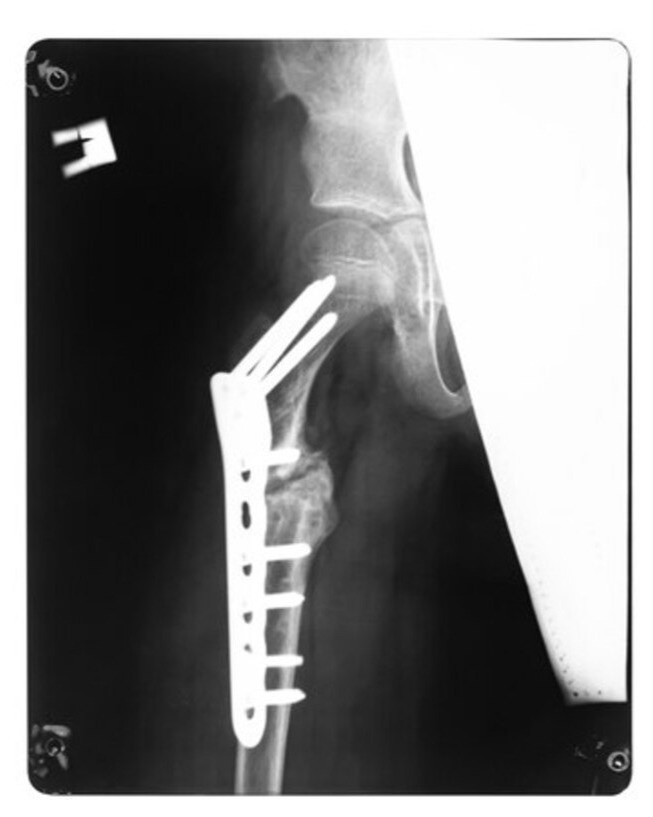

Megaprosthesis Surgery in Mumbai – Restoring Mobility After Bone Loss